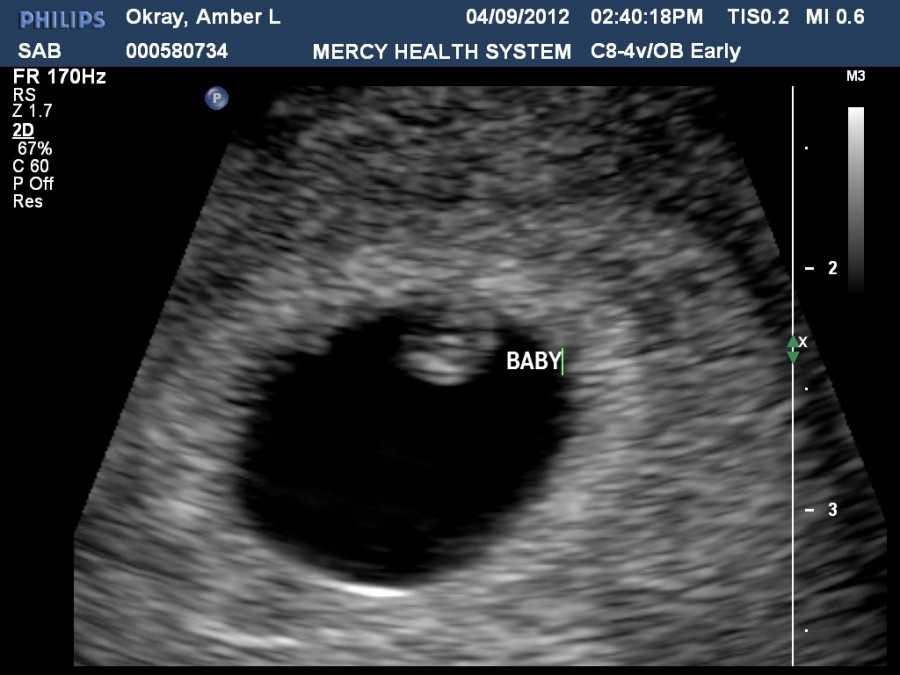

Вот так выглядит твой малыш на 9 неделе (фото плода)

Конечно, больше всего будущим родителям интересно знать, что происходит с малышом на 8–9 неделе. Он растет, и к этому сроку беременности длина плода уже достигает 2,5 см. Это примерно небольшая виноградинка или вишенка. Он свободно расположен в полости матки. При этом вес его составляет 4 грамма. Но, несмотря на небольшие размеры, при проведении ультразвукового исследования, у малыша уже можно различить личико и половой бугорок.

Также на врач может увидеть и сообщить родителям много другой полезной информации, а также показать плод на мониторе, присоединенном к датчику УЗИ. Эмбрион на 9 неделе жизни выглядит как человек, явно различимы голова, лицо с носиком и губами, ушные раковины, тельце, ручки и ножки с маленькими пальчиками. Но у ребенка все есть небольшой хвостик, а пропорции тела далеки от пропорций взрослого человека, и даже новорожденного. Голова эмбриона гораздо больше и доминирует над телом.

Фото плода и живота матери на сроке 9 недель

Как выглядит эмбрион на 9 неделе? Ваш кроха еще подрос. У него уже начинает формироваться личико, удлиняются конечности, появляются пальчики. Именно на данном этапе ребенок прогрессирует и становится не эмбрионом, а плодом, поскольку большой палец на руке разворачивается так, что прижимается к ладони с внутренней стороны (противостоящий палец).

Уже можно заметить пуповину. И именно с этой недели ваш малыш начинает развиваться быстрее вдвое.